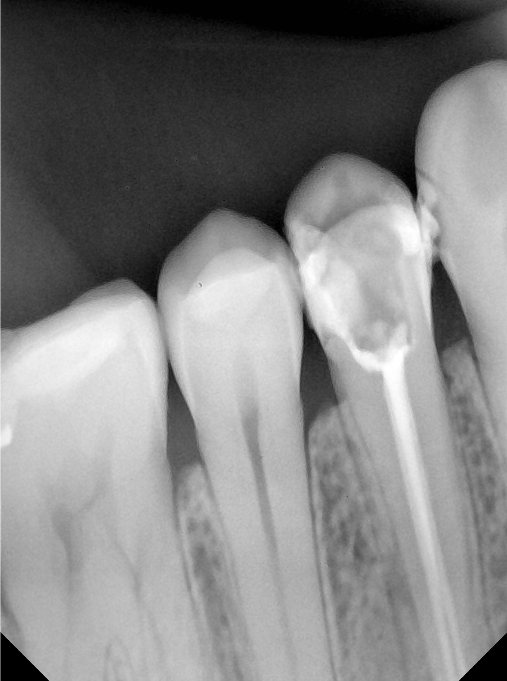

CR/DR 牙齿分割阶段记录

当前进展

- 完成了 CR/DR 牙齿相关分割训练

- 当前结果已经达到阶段预期,但仍有细节问题需要继续处理

相关测试

遇到的问题

- 训练过程中出现过 mask 下移问题

- 部分结果会出现 box 填充异常

- mask 边缘仍然有比较明显的锯齿感

第二版算法问题测试

| 第一版 | 第二版 | 是否解决 | |

|---|---|---|---|

![]() | ![]() ![]() 边角识别有问题 龋齿识别不全 牙髓识别不全 | ![]() | 解决 |

![]() | ![]() 边角识别有问题 识别信息有误 自查(牙冠识别不全) | ![]() | 解决 |

![]() | ![]() ![]() 边角识别有误 大范围填充识别遗漏 | ![]() | 解决 |

![]() | ![]() 识别信息不全 | ![]() | 解决 |

![]() | ![]() ![]() 边角问题 牙胶识别不全 牙冠识别不全 | ![]() | 解决 |

![]() 换图片 | ![]() | ![]() 牙冠部分稍微白了一些就识别成小范围修补,部分判断异常 | 部分解决,修复类略敏感,牙冠部分稍微白了一些就识别成小范围修补,部分判断异常。 |

![]() | ![]() ![]() 牙冠识别不全 牙髓不全 根尖炎龋齿识别有误 | ![]() | 解决 |

![]() | ![]() | ![]() | 解决 |

![]() 换图片 | ![]() | ![]() | 解决 |

![]() | ![]() 牙冠识别有误 | ![]() | 解决 |

![]() 换图片 | ![]() ![]() 边角识别有误 | ![]() 修复类敏感 | 部分解决,图像过白,导致修复类判断异常。 |

![]() 换图片 | ![]() 牙冠识别不全 | ![]() 修复类敏感 | 部分解决,图像过白,导致修复类判断异常 |

结论:修复类出现了不鲁棒的情况,后续需要加入轮廓的扩充数据进行增强。